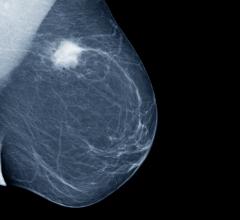

Nov. 19, 2024 — Results of a UCLA study recently published in the Journal of Breast Imaging demonstrates that Transpara ...

Despite decades of progress in breast imaging, one challenge continues to test even the most skilled radiologists ...

Nov. 12, 2024 — iCAD, Inc., a provider of clinically proven AI-powered cancer detection solutions, recently announced ...